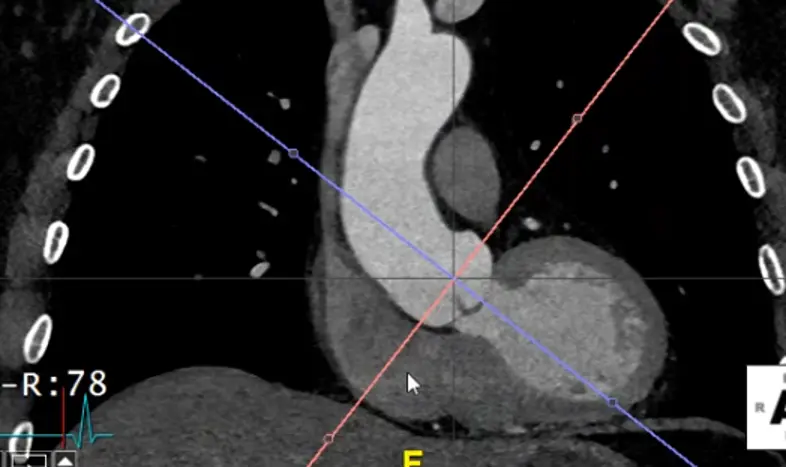

Xto grab your cross-hairs. You will drag the cross hairs to the middle of the sinuses of Valsalva in the axial view window. - In your coronal view window, there is a pink/red line with a small circle. Drag this circle to line up the pink/red line to be perpendicular to the wall of the sinus of Valsalva. The blue/purple line should be in the center of the long-axis of the aorta at the sinus of Valsalva.

- Similarly for your sagittal view, you will want your pink/red line to be perpendicular to the sinuses of Valsalva. You will also want your green line to be in the center of the long-axis of the aorta at the sinus of Valsalva.

- Once youâve lined things up, in your axial view window you will now have what is called a âtrue short axisâ of the aorta at that level.

Measure at sinuses of Valsalva

- Measure aortic root diameter at the sinuses of Valsalva on CT

- Drag the lines until you see the widest section in the coronal and sagittal planes

- Now in your axial view (SAX), you will measure commissure to sinus.

- RCC measurement:

- Normally, this will be from the commissure between the LCC and NCC

- You will then drag up to the sinus of the RCC

- NCC measurement:

- LCC and RCC commissure â sinus of NCC

- LCC measurement:

- RCC and NCC commissure â sinus of LCC

- You can also measure from sinus-to-sinus